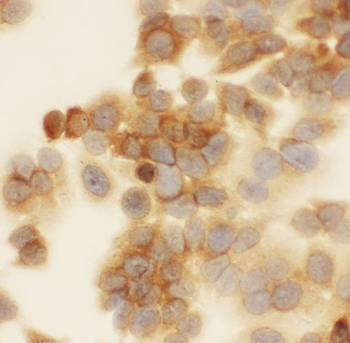

−| Tested Applications | ELISA, IHC |

| Dilution Range | IHC-P:1:20-1:200 |

| Immunogen | Recombinant Human Protein S100-A6 protein (1-90AA) |

| Target | S100A6 |

Immunohistochemical staining of human liver tissue using Prolactin antibody

S100A6 Antibody (orb239280)